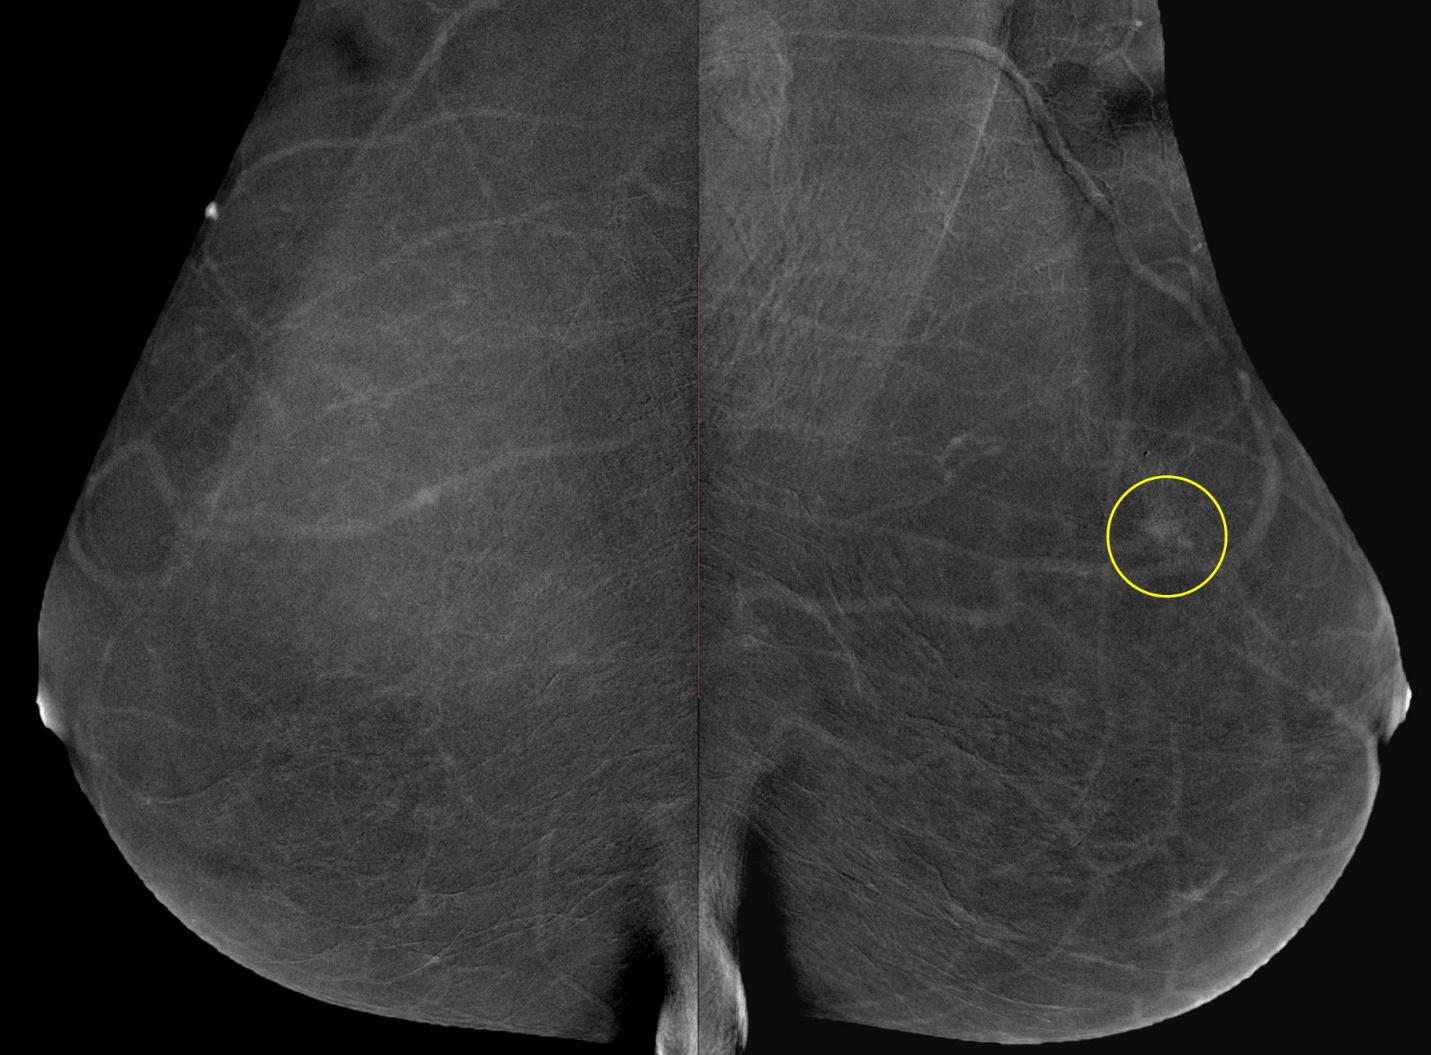

В зависимости от высоты устройства достигается коэффициент геометрического увеличения объекта исследования 1.5х, 1.8х или 2.0х.

Метод прицельной маммографии с увеличением применяется для более детального исследования определенной области молочной железы. Он отличается высокой точностью диагностики. В отличие от обычной маммографии, которая предоставляет более общую информацию о состоянии молочных желез, прицельная маммография с увеличением позволяет получить точные данные о процессах, происходящих в тканях, благодаря методу компрессии конкретного участка.